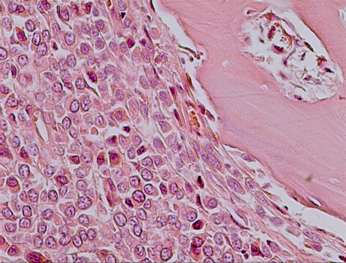

经组织学检查显示:镜下大量成骨细胞聚集,网状,细胞核细长,核质比高,深染细胞大量分布,非典型有丝分裂相较常见,部分区域有明显的成软骨细胞分布,骨质呈片状分布,组织间大量毛细血管网状分布,有出血,炎性细胞浸润(见图6-7)。淋巴结内大量圆形瘤细胞浸润,肿瘤已经淋巴结转移(见图8)。

图 6  大量成骨细胞聚集,细胞大小不一,核质比高,有毛细血管分布,

出血(黑色箭头所指),炎性细胞浸润(白色箭头所指)。(H.E.×100)

图 7  骨肉瘤。细胞核细长,非典型有丝分裂相常见。(H.E.×400)

图 8  骨肉瘤淋巴结转移。淋巴结内有大量圆形瘤细胞浸润(箭头所指)。(H.E.×400)